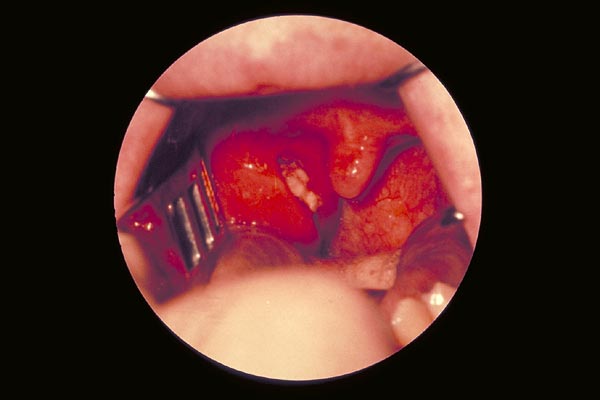

Tonsillitis mit Epitheldefekt

|

Angina Plaut-Vincent